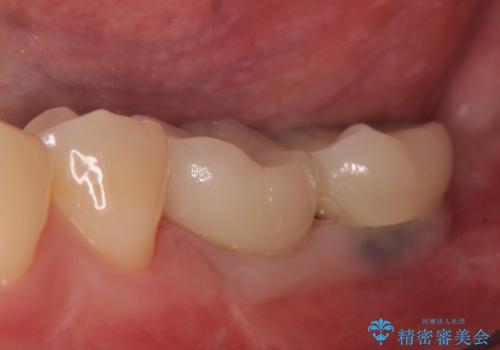

オールセラミッククラウンについて

今回用いたオールセラミッククラウンはジルコニアフレームという白い素材の上にセラミックを盛っているため、審美性が非常に高いのが特徴です。

また、ジルコニアは人工ダイヤモンドの材料にも使われているほど高い強度を持っており、そのためオールセラミッククラウンは審美性だけでなく、奥歯やブリッジの補綴も可能とするクラウンです。